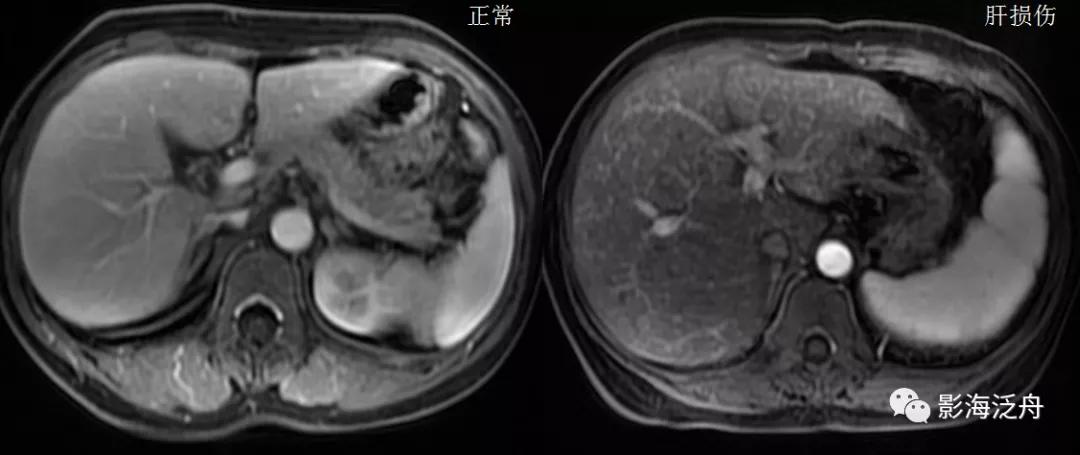

将正常人与该患者的T2WI抑脂序列放在一起对比观察。在抑脂较均匀的区域,可以发现该患者肝实质的T2WI信号轻度增高(红箭),门静脉周围的胆管间隙增宽(绿箭),肝周间隙缩小(蓝箭)提示肝脏肿大,脾大(黄箭)。

增强动脉期,患者肝实质呈弥漫性斑点状强化(类似于粟粒型肺结核),这种强化方式可能与动脉及门脉的细小分支异常分流及部分肝组织灌注不良有关。门脉期及静脉期患者肝实质呈较均匀强化(未给出图像),提示病程相对可逆。

与正常人对比可以更好地观察上述图像特征,注意肝损伤患者的肝脏强化程度整体较低(以脾脏强化程度作为参照,两幅图像的强化时间大致相仿),但平衡期强化程度并无异常减低(未给出图像)。